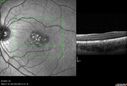

Laser pointer maculopathy77 views11 year old male When school started the patient noticed that he was having trouble reading and seeing out of both eyes. There are no retinal diseases in the family.

VA OD: sc20/25

VA OS: sc20/40

TP: OD:19 OS:18